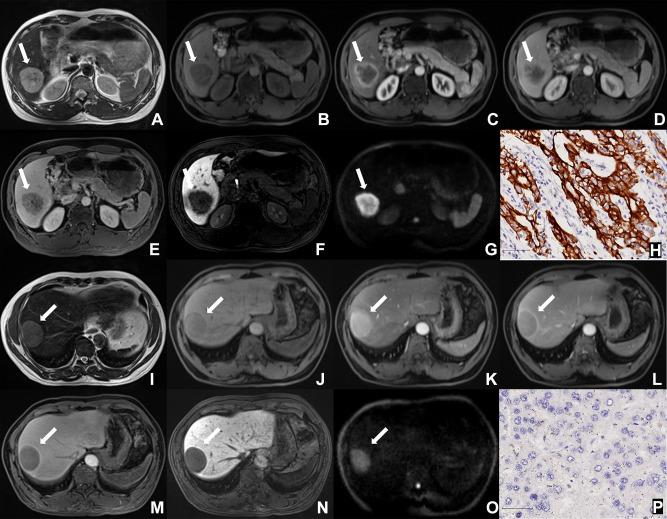

Cytokeratin 19 (CK19) expression is a proven independent prognostic predictor of hepatocellular carcinoma (HCC). This study aimed to develop and validate the performance of a deep learning radiomics (DLR) model for CK19 identification in HCC based on preoperative gadoxetic acid-enhanced magnetic resonance imaging (MRI).

A total of 141 surgically confirmed HCCs with preoperative gadoxetic acid-enhanced MRI from two institutions were included. Prediction models were established based on hepatobiliary phase (HBP) images using a training set (n=102) and validated using time-independent (n=19) and external (n=20) test sets. A receiver operating characteristic curve was used to evaluate the performance for CK19 prediction. Recurrence-free survival (RFS) was also analyzed by incorporating the CK19 expression and other factors.

For predicting CK19 expression, the area under the curve (AUC) of the DLR model was 0.820 (95% confidence interval [CI]: 0.732-0.907, <0.001) with sensitivity, specificity, accuracy of 0.800, 0.766, and 0.775, respectively, and reached 0.781 in the external test set. Combined with alpha fetoprotein, the AUC increased to 0.833 (95% CI: 0.753-0.912, 0.001) and the sensitivity was 0.960. Intratumoral hemorrhage and peritumoral hypointensity on HBP were independent risk factors for HCC recurrence by multivariate analysis. Based on predicted CK19 expression and the independent risk factors, a nomogram was developed to predict RFS and achieved C-index of 0.707.